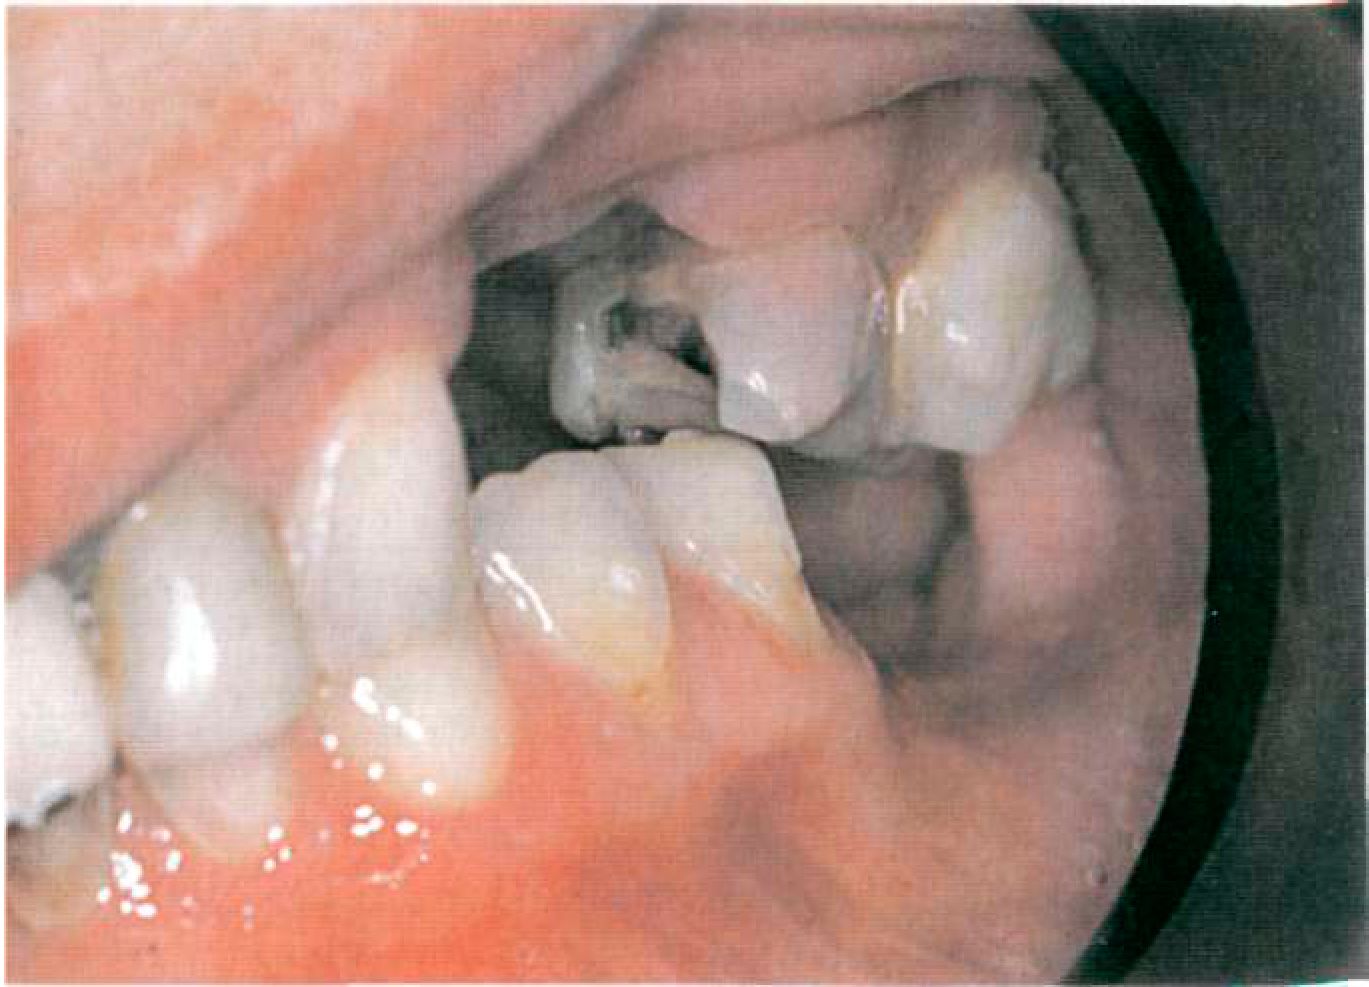

Для клинической ситуации, представленной на рисунке 117, было выбрано несъемное протезирование мостовидным протезом на верхней челюсти и малый седловидный протез нижней челюсти с замковым креплением Deguswing. Этап 3. Проектирование протеза на диагностических моделях, определение плана подготовки полости рта к протезированию. Этап 4. Препарирование опорных зубов. Жевательные опорные зубы препарируют с круговым поддесневым или придесневым уступом в 135° и сохранением высоты коронковой части не менее 5 мм (рис. 118).

В данной клинической ситуации оттиск препарированных опорных зубов и челюстей снимали, используя поливинилсилоксановую массу «Dentstar» (Германия), препарированные зубы покрывали временными коронками (рис. 119). Этап 5. Изготовление каркаса коронок опорных зубов с патрицей или матрицей аттачмена, установленной в параллелометре. В случае замкового крепления Deguswing на восковые колпачки опорных коронок устанавливается патрица аттачмена (рис. 120). Этап 6. Примерка каркаса коронок опорных зубов во рту (рис. 121). Выбор цвета керамической облицовки. Этап 7. Примерка коронок опорных зубов с облицовкой (рис. 122). Коррекция окклюзии, цвета.